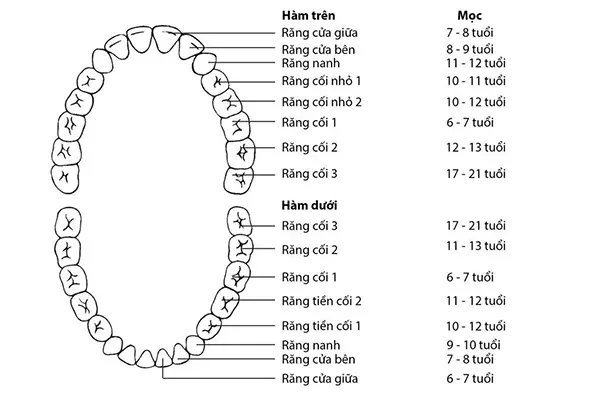

Câu hỏi “con nguoi co bao nhieu rang” luôn là thắc mắc phổ biến của nhiều người khi muốn hiểu rõ hơn về sức khỏe răng miệng.

Chân răng số 6 là một phần quan trọng của răng số 6, một trong những chiếc răng vĩnh viễn lớn, đóng vai trò chủ chốt trong